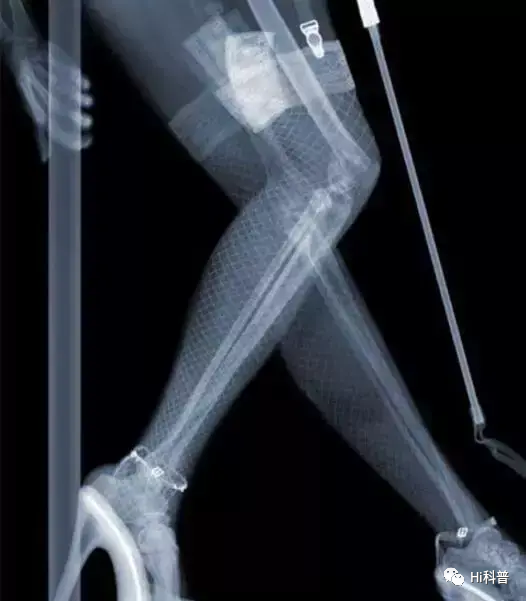

而X射线是一种频率范围在30PHz~300EHz之间,对应波长为1pm~10nm,能量为124eV~1.24MeV的电磁波,能量很大,具有穿透性。 能够直接透过人体的不同组织和杂乱的物品,但由于物质的密度和厚度不一样,被吸收的程度也不同,最终显像处理后,才能得到不同的影像。 工作人员可以根据这些影像,判断你带的东西,是否为违禁物品。 部分不法分子铤而走险,甚至将枪藏于屁股处,企图蒙混过关,最终都被拦下来,还有乘客带的各种奇葩东西,都能看得清清楚楚。

所以,不要妄想不会被发现,安检可是很严格的,包括你身体的每个部位,都一览无余,就连整容人士身上的金属和硅胶,都能清晰看到。 至于隐私,完全可以放心,只有工作人员能看到,其他人想要靠近仪器屏幕,基本是不可能的。更何况去医院检查,也是运用到X光,只会照射到骨骼,不用担心这个问题。 而这是工作人员的本职工作,每天兢兢业业,眼睛始终盯着屏幕,又怎么会尴尬呢?尴尬的应该是被拦下,要求开箱检查那类人。